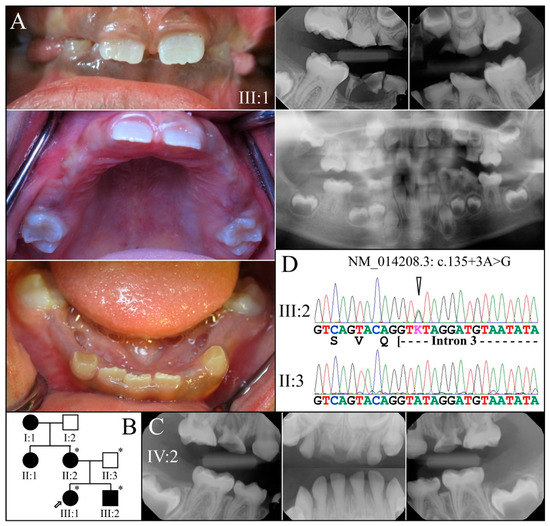

| 11 | Intron 2 | g.8576G>A | c.52-1G>A | p.(?) | Family 2, [69] |

| 21 | Intron 3 | g.8663A>G | c.135+3A>G | p.(?) | Family 4 [78] |

| 2 | Illumina HiSeq 2500 (WES) | NG_011595.1:g.8576G>A; NM_014208.3:c.52-1G>A | Splice Acceptor | IV:2, affected 2nd child: 177.72× |

| 4 | Sanger Sequencing | NG_011595.1:g.8663A>G; NM_014208.3:c.135+3A>G | Splice Donor | |